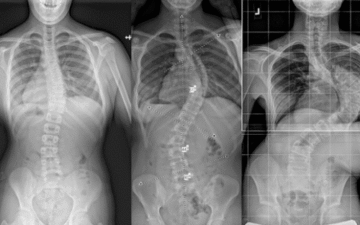

لماذا يتأخر الأهل في علاج اعوجاج العمود الفقري عند الأطفال؟ الأسباب الحقيقية وكيف تتجنبها يُعد اعوجاج العمود الفقري عند الأطفال من الحالات التي تحتاج إلى تدخل مبكر لتحقيق أفضل النتائج. ومع ذلك، يلاحظ الأطباء

هل يمكن علاج اعوجاج العمود الفقري عند الأطفال بالحزام؟ نتائج حقيقية لحزام PioBrace خلال 12 شهر يُعد اعوجاج العمود الفقري عند الأطفال من أكثر الحالات التي تُقلق الأهل، خاصة عندما يظهر في سن مبكر

مخاطر تأخر علاج اعوجاج العمود الفقري عند الأطفال: التدخل المبكر ينقذ مستقبل طفلك عندما يتم تشخيص الطفل بـ اعوجاج العمود الفقري، قد يعتقد بعض الأهل أن الحالة بسيطة ويمكن الانتظار قبل بدء العلاج. لكن